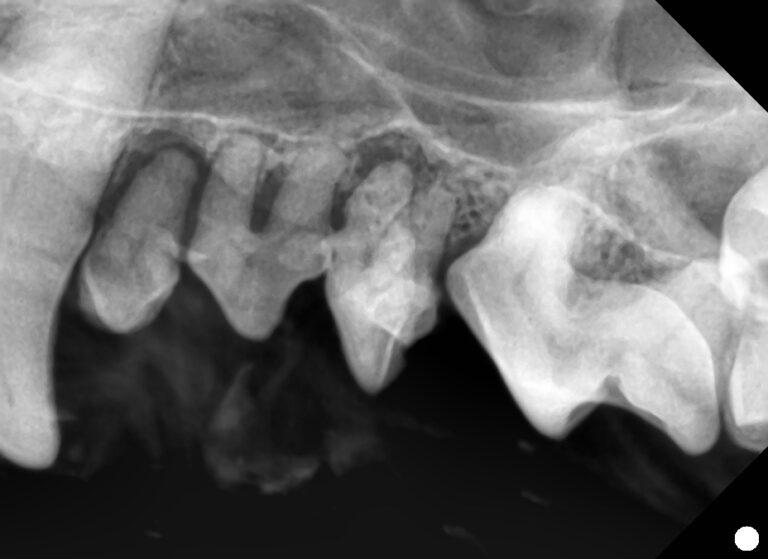

【歯科】小型犬に多い小臼歯の叢生と歯周病リスク

【歯科】破折歯・露髄のリスクと根管治療の流れを解説〜犬の歯が折れたら〜

【歯科】口の中にできたしこりの正体は?〜末梢性歯原性線維腫(良性腫瘍)〜